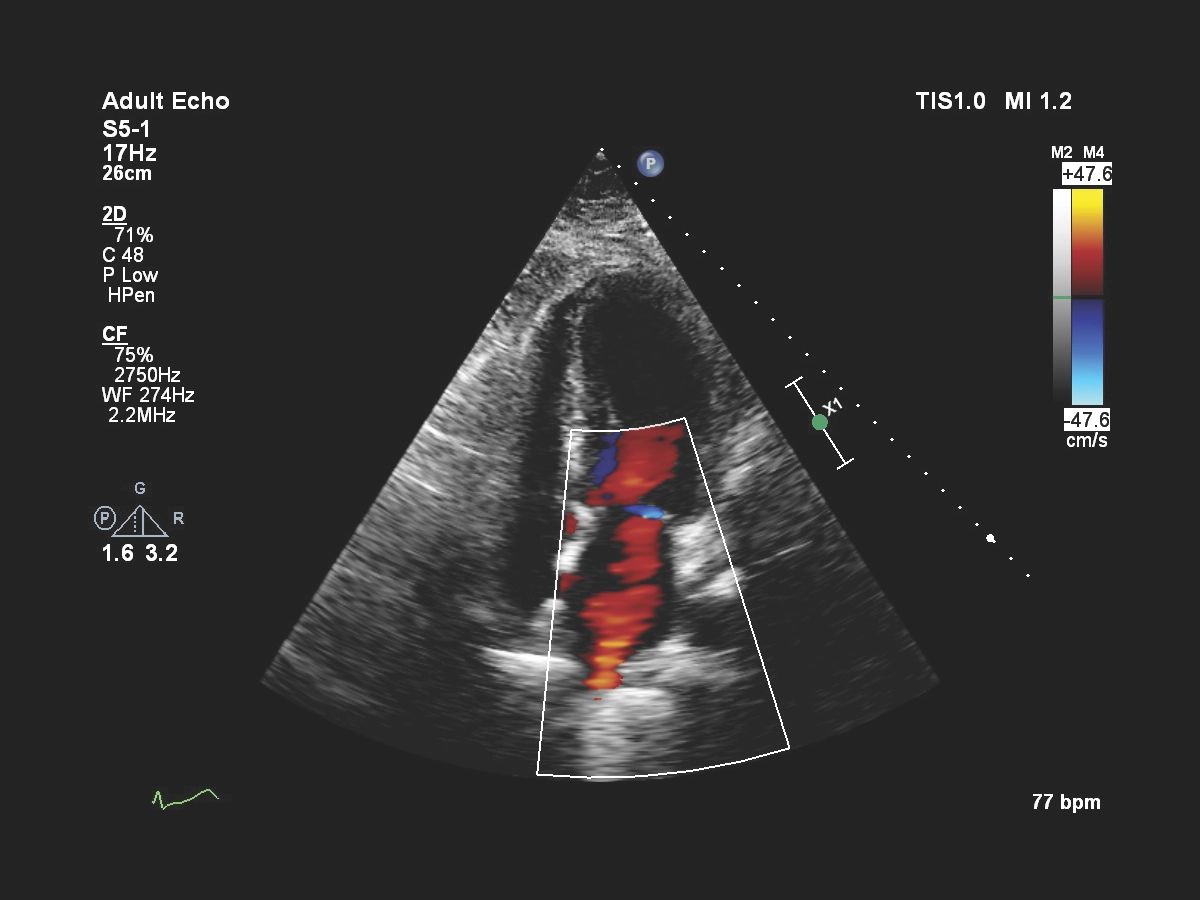

- Кардиология

Функции для кардио-исследований

- 2D B, M-режим, ЦДК

- Энергетический доплер CPA